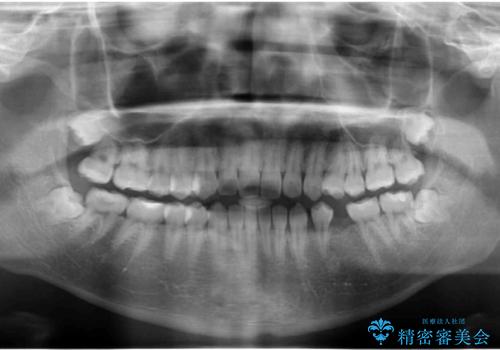

- 左下の奥歯が生まれつき歯が少ない患者様です。

健康な歯を削らずに歯を入れたいとのことでした。

歯がなかった時期に隣の歯が移動してすき間があったため、部分的な矯正治療を行い、インプラントを入れるすき間を確保しています。

通常矯正治療は後戻りがあるので保定が必要です。

しかし、今回は不要でした。

矯正治療で歯を移動して得られたすき間はインプラントのクラウンで動かないようにできるためです。

保定が不要という点におきましては、部分矯正と補綴(被せ物)治療は非常に相性がよく、得られるメリットも大きいといえます。